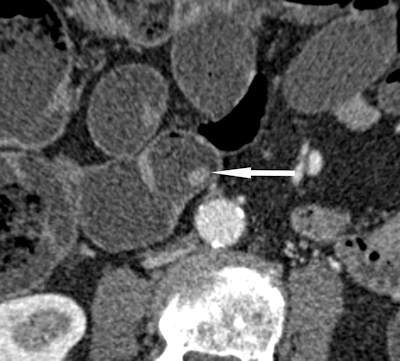

CT enterography has major limitations in the evaluation of OGIB, according to Soyer. This is because vascular abnormalities account for 80% of OGIB, and especially angiodysplasia, which accounts for 50-60% of OGIB, whereas small bowel tumors are found in only 1.6% to 2.4% of patients undergoing VCE.

"VCE allows direct visualization of the small bowel mucosa and has a high sensitivity for the detection of flat lesions such as ulcers, angiodysplasias, or arteriovenous malformations, which are lesions beyond the reach of the best CT resolution available," he noted. "VCE shows ulcers and angioectasias that are not visible at CT enteroclysis. A large number of papers have showed that among the variable causes of OGIB, the one most commonly missed at CT enterography was small-bowel angioectasia."

Khalife S, Soyer P, Alatawi A, Vahedi K, et al. Obscure gastrointestinal bleeding: Preliminary comparison of 64-section CT enteroclysis with video capsule endoscopy. Eur Radiol. 2011;21(1):79-86.